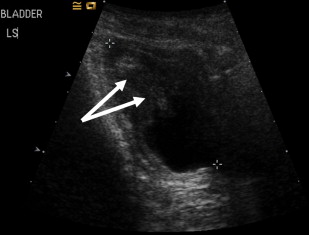

Severe constipation in patients with severe generalized recessive DEB may also result in urinary outflow obstruction with hydroureter and hydronephrosis ( Figs. 2 and 3 ), which may resolve on adequate treatment of the constipation (J.E. Mellerio, personal communication, 2009).